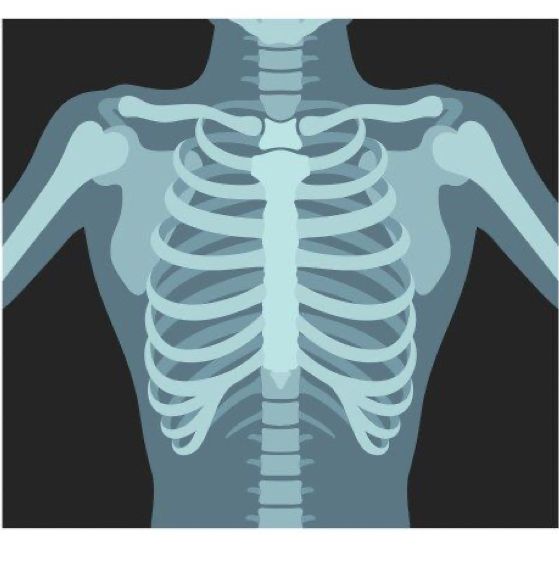

X-Ray

An X-ray is a type of medical imaging test that uses a small dose of electromagnetic radiation to create pictures of the inside of the body. It is one of the most common and widely used diagnostic tools in healthcare because it helps doctors see bones, joints, and certain tissues without the need for surgery. X-rays work by passing radiation through the body; dense structures like bones absorb more rays and appear white on the image, while softer tissues allow more rays to pass through and appear darker.

X-rays are used for many purposes in medicine. They are most commonly performed to detect broken bones, fractures, and joint dislocations. They are also used to diagnose conditions such as pneumonia, infections, arthritis, dental problems, kidney stones, and certain types of tumors. Specialized X-ray techniques, such as mammography, are used to detect breast cancer, while chest X-rays can help evaluate lung and heart conditions. Sometimes a contrast dye is used during an X-ray procedure to make certain organs, blood vessels, or tissues more visible.